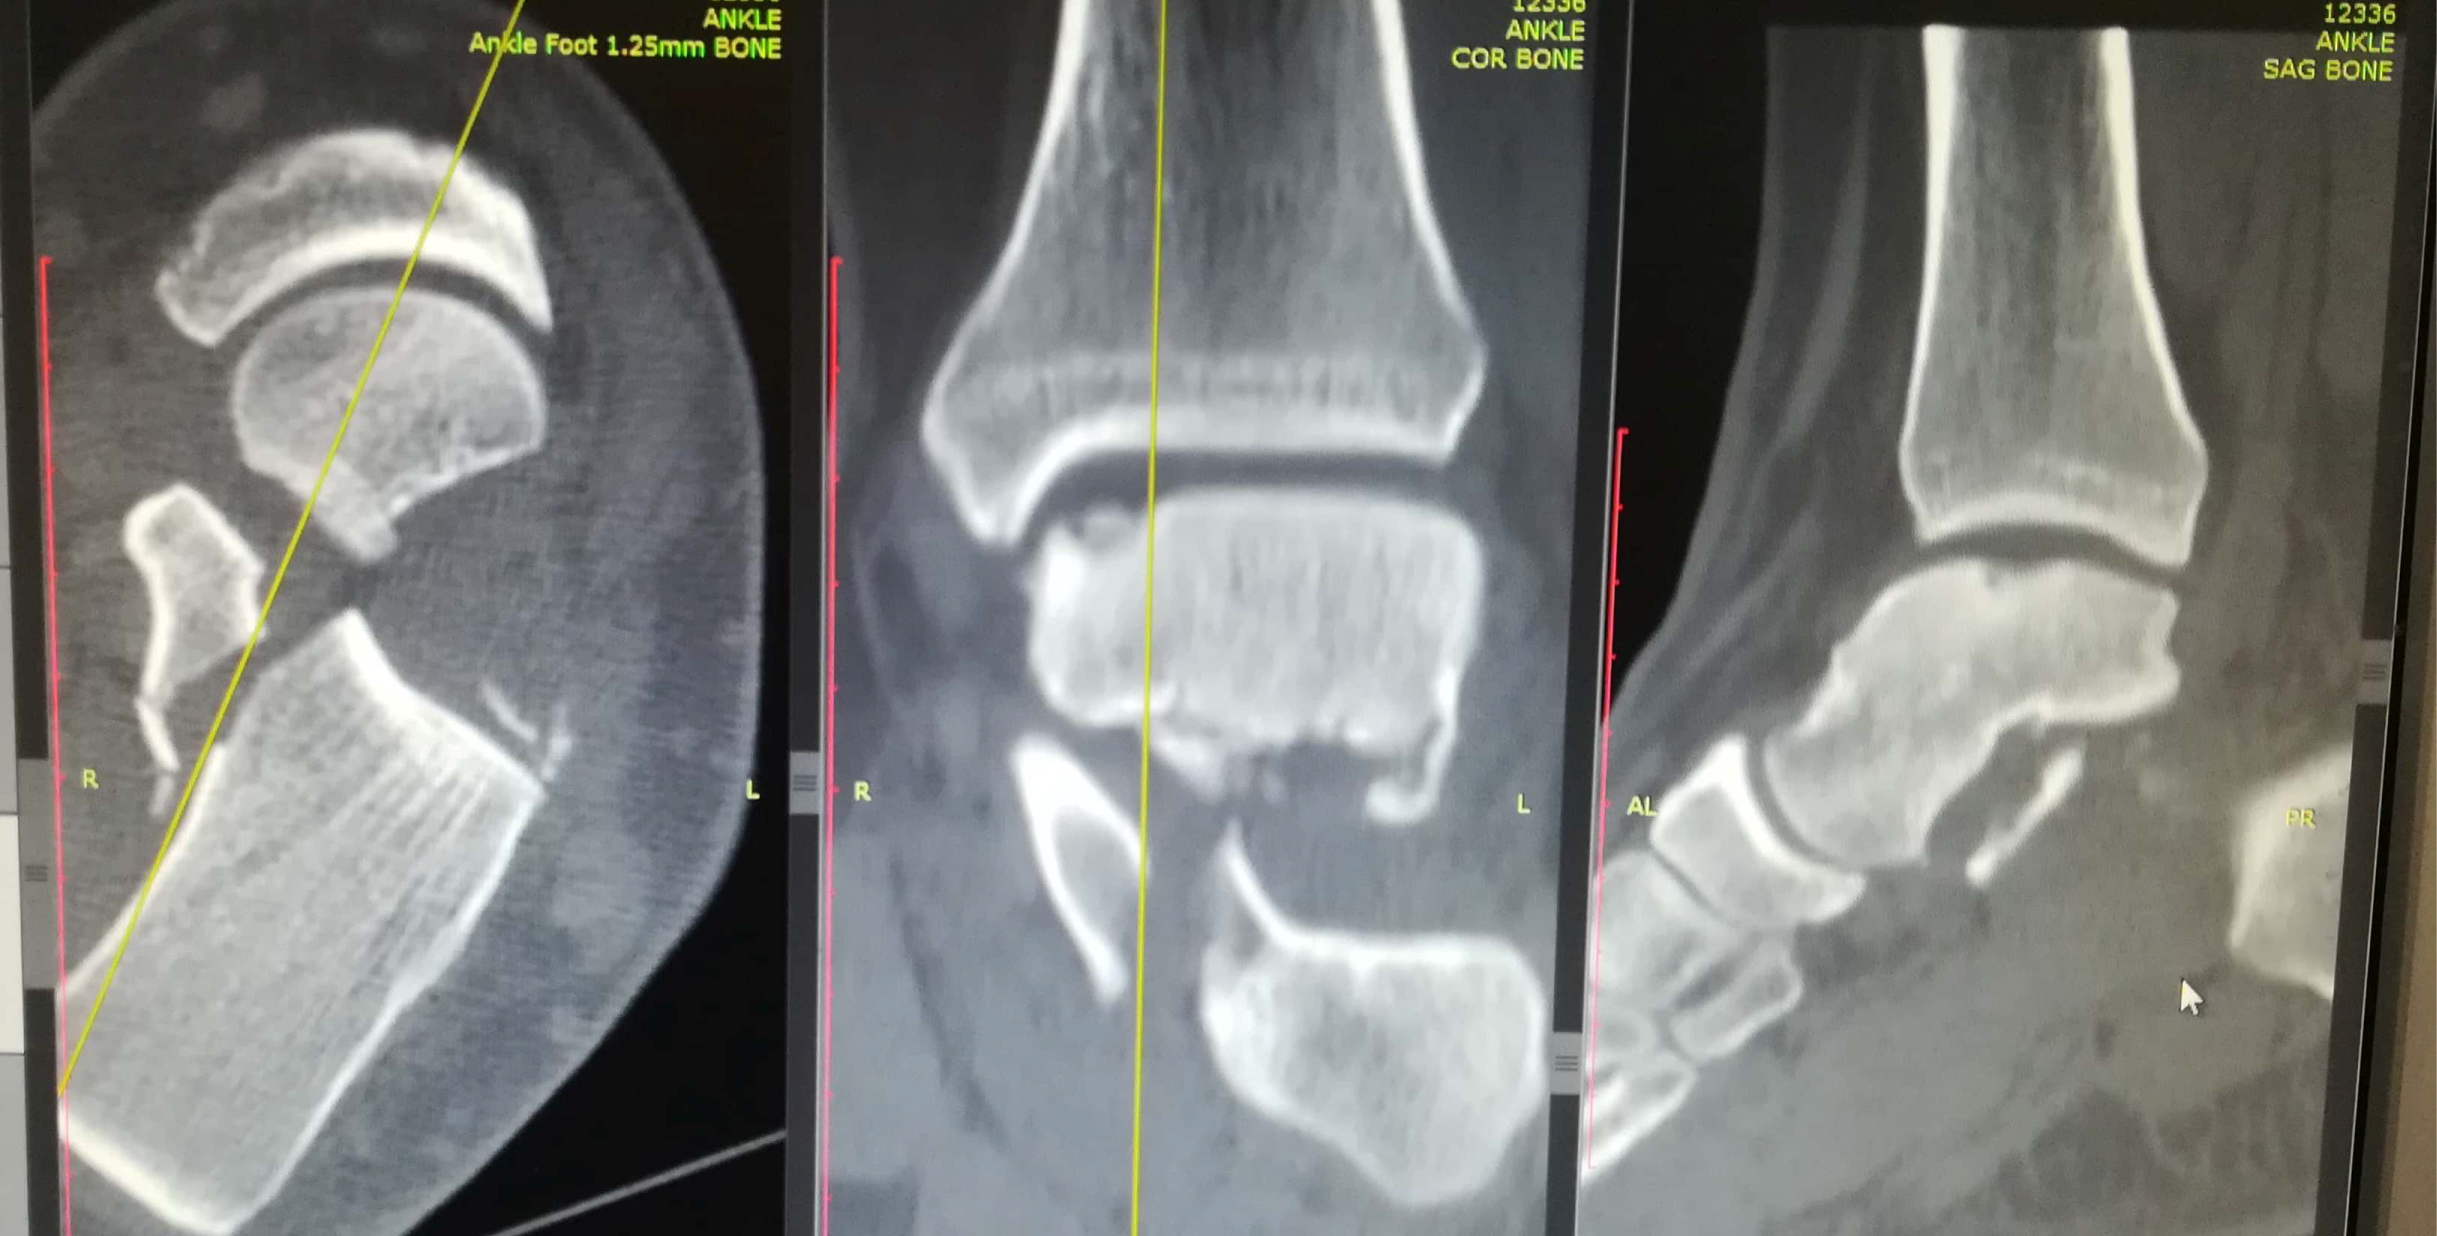

Anteroposterior, mortise and true lateral views of the left foot and ankle radiographs were obtained (Figure 1 and Figure 2). A displaced lateral talar body fracture and subtalar joint disruption, as well as a tilt of the tibiotalar joint, were revealed from the plain radiographs. Osteochondral defect on the medial side of the dome of the talus, due to an old ankle injury, sustained few years ago, was also visible. CT scan of the left foot confirmed a displaced lateral talar body fracture along with a displaced sustentaculum tali fracture (Figure 3, Figure 4 and Figure 5).

Figure 3: Ankle CT scan showing lateral talar body fracture with subtalar subluxation. View Figure 3

Figure 4: Ankle CT scan showing sustentaculum tali fracture with gross displacement. View Figure 4

Figure 5: Ankle CT scan showing lateral talar process fracture with comminution. View Figure 5